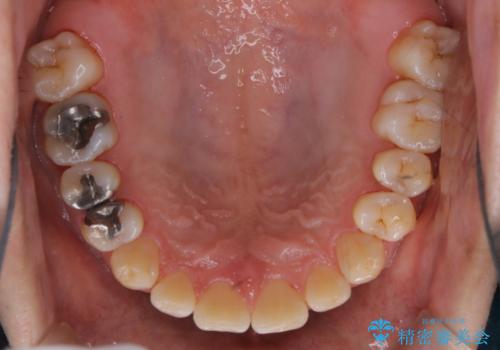

タバコとコーヒーによる頑固な着色落とし

- 毎日の喫煙とコーヒーを飲むことにより、ひどく着色がついてしまったとのことです。PMTC60分コースを行いました。